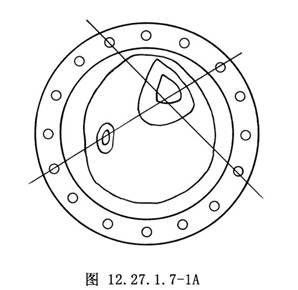

(1)小腿部件的安裝:在小腿中份相距4~6cm的兩個平面,分別經皮鑽入兩組交叉克氏針(直徑1.5~3.0mm,根據患肢的大小選擇,交叉角度40°~80°),克氏針垂直於小腿長軸,其中一枚克氏針同時貫穿脛、腓骨,另一枚僅貫穿脛骨(圖12.27.1.7-1A);將兩個平面的克氏針分別固定在兩個全環部件上,並將兩個全環用連桿連接固定成爲一個整體。

(1)小腿部件的安裝:在小腿中部相距4~6cm的兩個平面,分別經皮鑽入兩組交叉克氏針(直徑1.5~3.0mm,根據患肢的大小選擇,交叉角度40°~80°),克氏針垂直於小腿長軸,其中1枚克氏針同時貫穿脛、腓骨,另1枚僅貫穿脛骨(圖3.19.1.4-1);將兩個平面的克氏針分別固定在兩個全環部件上,並將兩個全環用連桿連接固定成爲一個整體。